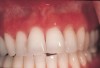

Most of the erythema was observed in the attached gingiva. Twenty cases (54%) included a description of diffuse or generalized erythema of the attached gingiva (Figure 1). Fifteen of these cases were caused by toothpaste. A “velvet-like appearance of gingiva” was a symptom in Cases 4, 6, and 33. Case 27 contained the description “fiery red gingiva.” In 17 cases, gingival erythema was observed in the anterior facial area. Of these, 6 cases (Cases 4, 18, 21, 25, 27, and 35) also showed erythema in the labial mucosa that was in contact with the inflamed facial gingiva. Four cases (Cases 24, 30, 31, and 37) showed gingival erythema in the palatal area.

The cinnamon-containing substance that caused contact stomatitis in most cases was toothpaste. Tartar-control toothpastes usually contain tetrasodium or tetrapotassium pyrophosphates as their anticalculus component.16 Because pyrophosphates have a strong, bitter taste, large quantities of cinnamon flavoring agents are needed in tartar-control toothpastes to mask that taste.16 Cinnamon-induced contact stomatitis caused by toothpaste occurred in various sites, but the gingiva was the most common. Diffuse or generalized erythema was found in the attached gingiva. This characteristic was seen in 20 cases (54%); most were caused by toothpaste. The facial and the palatal/lingual gingiva was affected, but the anterior facial changes were more pronounced. Erythema was described as a “velvet-like appearance of the gingiva” or “fiery red gingiva.” These clinical features were similar to those previously reported as plasma cell gingivitis.17,18 Epithelial sloughing was also most frequently noted in the gingiva. Epithelial sloughing is the most common irritant effect associated with toothpastes and mouthrinses.19 Toothpaste was the cause for 7 of the 9 patients with epithelial sloughing in this study.

Figure 1  Diffuse erythematous gingiva of upper arch (Case 16).

Figure 1